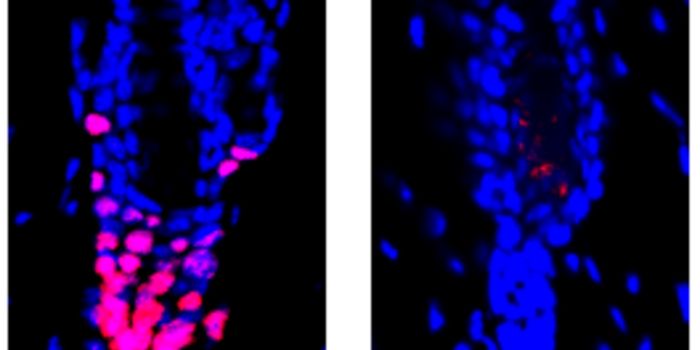

JUN 25, 2022ImmunologySalk Institute researchers studying alopecia have learned more about the link between immunity and hair growth.

SEP 27, 2021Genetics & GenomicsWhile this research has provided some answers, it also raised many new questions. An image by Atish Waghwase/Harney et a ...